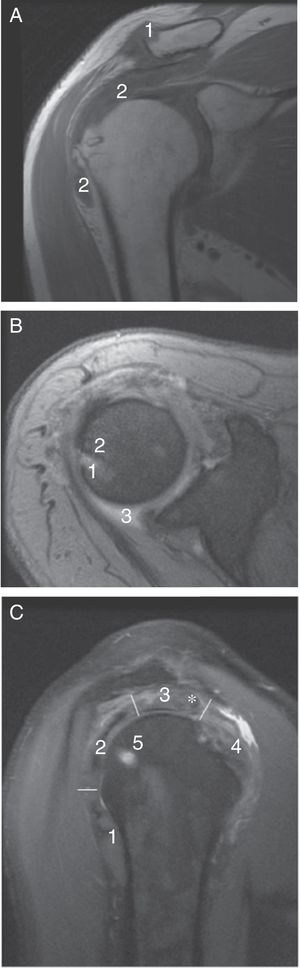

A) Imagen por RM de hombro derecho en adquisición coronal en secuencia potenciada en T1. En una imagen superponible a la radiografía de la figura 1 B se observan los tofos como masas de tejidos blandos hipointensas en T1 en el borde superior del extremo clavicular distal (1) y en la bursa subacromiodeltoidea (2). B) Imagen en adquisición axial T2 eco de gradiente. La RM revela una lesión compatible con tofo gotoso (1) en el borde articular glenohumeral no claramente visible en la radiografía simple. Es hiperintenso en secuencia potenciada en T2, interrumpe la corteza ósea y tiene un reborde muy hipointenso por la esclerosis ósea (2). Se asocia un discreto derrame synovial (3). C) Imagen en adquisición sagital en densidad protónica que permite ver la sección de los tendones que forman en manguito de los rotadores: redondo menor (1), infraespinoso (2), supraespinoso (3) y subescapular (4). El supraespinoso está especialmente desestructurado por la presencia de un nódulo sugestivo de tofo intratendinoso (*). Como en la secuencia potenciada en T2, el tofo óseo es hiperintenso (5).